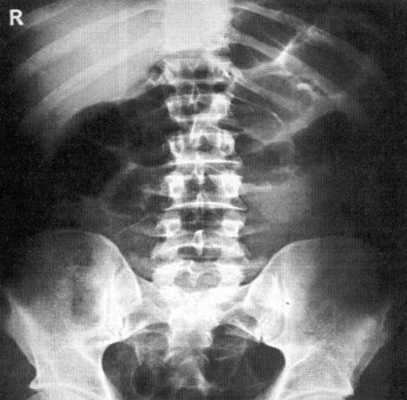

Рентгенография брюшной полости

Рентген активно используется для диагностики заболеваний органов брюшной полости. Широко распространена обзорная рентгенография брюшной полости - рентгенографическое исследование без введения контрастного вещества, позволяющая получить общую картину состояния брюшной полости.

Брюшная полость - это полость живота, которая ограничена сверху диафрагмой, спереди - брюшной стенкой, сзади - поясничной частью позвоночника, с боков - мышцами живота, снизу - подвздошными костями и диафрагмой таза. Внутри брюшной полости находятся органы пищеварительной системы - желудок, желчный пузырь, печень, кишечник, поджелудочная железа а также селезенка и органы мочевыделительной системы - почки и мочеточники.

Что показывает рентген брюшной полости?

Метод рентгендиагностики основан на том, что ткани различной плотности по-разному поглощают рентгеновские лучи. Более плотная, например, костная ткань хуже пропускает лучи, поэтому на снимке такая ткань оказывается светлее. Метод позволяет определить местоположение органов, их целостность, наличие инородных тел и новообразований.

Рентгенография брюшной полости показывает:

- как распределены газ и жидкость в брюшной полости, присутствует ли в брюшной полости свободная жидкость;

- присутствуют ли в брюшной полости инородные тела (проглоченные предметы в кишечнике, камни в желчном пузыре, камни в почках);

- имеются ли повреждения внутренних органов;

- имеет ли место внутрибрюшное кровотечение.

Рентген брюшной полости

С точки зрения оценки состояния конкретных органов обзорная рентгенография брюшной полости не очень информативна, однако она позволяет быстро определить, является ли картина патологической или нет. При разрыве стенки желудка или кишечника (прободение язвы или разрушении стенки опухолью) рентген покажет выходящий в свободную брюшную полость газ. С помощью рентгена брюшной полости можно диагностировать непроходимость кишечника и даже определить примерное место локализации проблемы.

Когда назначается рентген брюшной полости?

Обзорная рентгенография брюшной полости назначается при наличии жалоб на сильные боли в животе. Подобные боли могут наблюдаться при следующих заболеваниях:

Как проводится рентгенография брюшной полости?

Для обзорной рентгенографии брюшной полости специальной подготовки не требуется.

Рентгенография может быть выполнена как в одной, так и в двух проекциях (в положениях стоя и лежа). Иногда достаточно сделать рентген только в положении стоя (такая позиция позволяет лучше локализовать проблему при непроходимости кишечника, а также увидеть прободение желудка или кишечника).